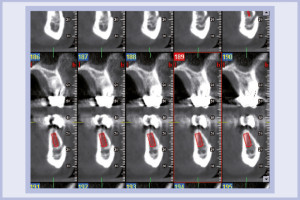

Per riabilitare la masticazione del terzo quadrante, con osso gravemente atrofico, si procede allo studio del caso con esame radiologico 3D e posizionamento virtuale di impianti Exacone® Leone. La prima valutazione è stata eseguita con il software dell’apparecchio radiografico Cone Beam presente in studio. Dopo aver verificato che la quantità di osso residuo fosse sufficiente all’inserimento di due impianti, seppur di dimensioni ridotte, in sede 3.5 e 3.6 senza l’ausilio di tecniche di rigenerazione ossea (Figg. 1-3), si richiede al laboratorio di confezionare una mascherina radiologica con ceratura diagnostica radiopaca e repere standardizzato a livello incisale come da protocollo Leone (Figg. 4, 5). Si verifica quindi clinicamente l’assenza di mobilità della mascherina dopo il posizionamento nel cavo orale del paziente (Figg. 6, 7). Si effettua una CBCT con la mascherina in posizione e l’esame viene inviato in formato DICOM all’azienda Leone assieme al modello master della paziente. L’azienda provvede quindi ad inviare agli Autori il software 3Diagnosys (software di progettazione) in licenza monopaziente con caricati i file DICOM ricevuti; il software viene quindi utilizzato per la progettazione definitiva del caso (Figg. 8-12).

- Figg. 1-3 – Esame Cone Beam iniziale, si verifica la fattibilità di inserimento impianti

- Fig. 2 mento impianti

- Fig. 3